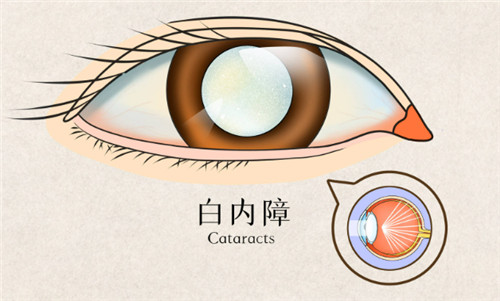

在眼科医疗领域,德国制造常被视为品质与技术的代名词。作为德国本土深耕眼科器械的品牌,德国人类光学(Human Optics)凭借其人工晶体产品,在白内障、老花眼等视力矫正领域占据重要地位。